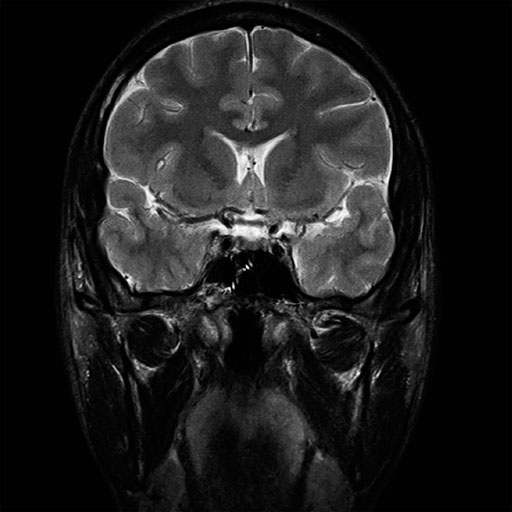

Sagittal T2w TSE images of the brain (left:

without motion correction; right: with syngo BLADE) |

Coronal T2w TSE images of the brain (left: